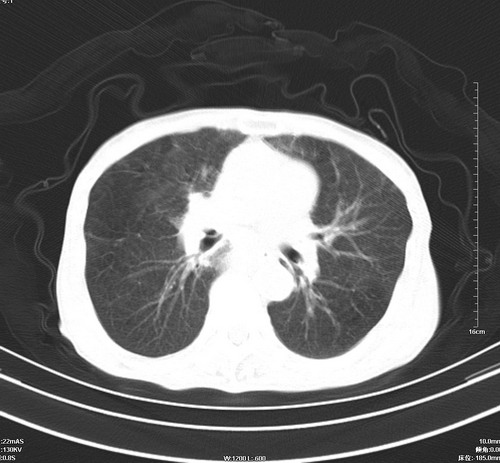

中后纵隔占位,气管、食道受压、变形、移位。恶性可能性大。

1 气管旁、隆突下淋巴结明显肿大,肝左叶外侧段低密影,都考虑转移。

纵隔淋巴结肿大,考虑转移而来

肺癌,纵隔淋巴结转移,肝左叶病变考虑为转移病灶。

后中纵隔团块影,伴气管、食道受压移位,首先考虑转移瘤,肝s5段低密度灶。建议增强检查,另外其结肠是否有问题请提供,右肺部分肺叶局限含气增多,考虑局限肺气肿。

建议强化检查,考虑纵隔型肺癌,小细胞可能性大。

后中纵隔淋巴结肿大,首先考虑转移瘤。